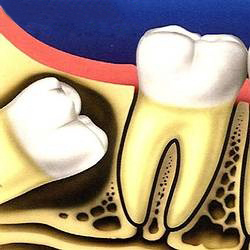

Nhưng thực tế là ta có tới 32 răng vì thêm 4 răng khôn, 2 ở hàm trên và 2 ở hàm dưới và mọc sau cùng. Phiền toái xảy ra khi chúng không đủ chỗ để mọc theo hướng bình thường mà tự tìm đường khác, ví dụ như mọc ngược về phía xương hàm hoặc đâm thẳng về phía răng hàm lớn thứ hai ở bên cạnh. Chúng có thể mọc bình thường, nhú lên khỏi lợi được một phần thì bị tắc và ngừng lại vĩnh viễn.

Do đó nếu người ở độ tuổi 23-25 mà chưa nhìn thấy răng khôn của mình mọc lên hoặc chỉ nhìn thấy một phần của răng, gần như chắc chắn là răng khôn của bạn đã mọc lệch.